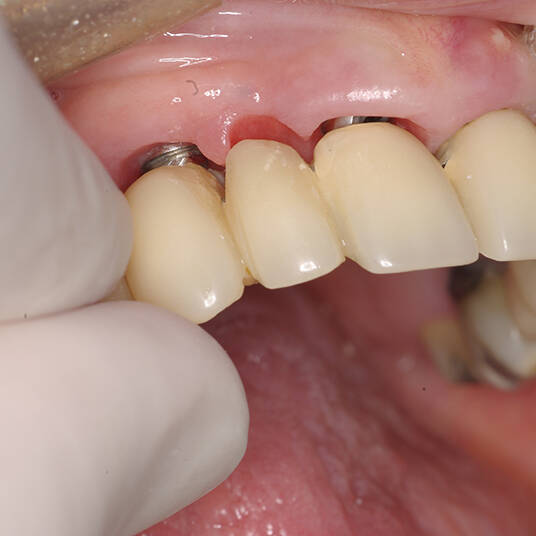

Na Clínica Pontes Odontologia, somos referência em implantes dentários em Fortaleza, oferecendo tratamentos de alta qualidade e tecnologia de ponta. Os implantes dentários são estruturas de titânio posicionadas cirurgicamente no osso maxilar ou mandibular para substituir as raízes dos dentes ausentes. Essa técnica permite a fixação de próteses personalizadas, restaurando a função mastigatória, a estética e a autoestima dos nossos pacientes.

Utilizamos a tecnologia CAD CAM, um sistema avançado que possibilita a confecção precisa das próteses dentárias diretamente sobre os implantes. Esse método inovador garante um ajuste perfeito, um resultado estético superior e proporciona muito mais conforto e durabilidade. Com o CAD CAM, nossos pacientes contam com um processo mais rápido e previsível para alcançar o sorriso desejado.